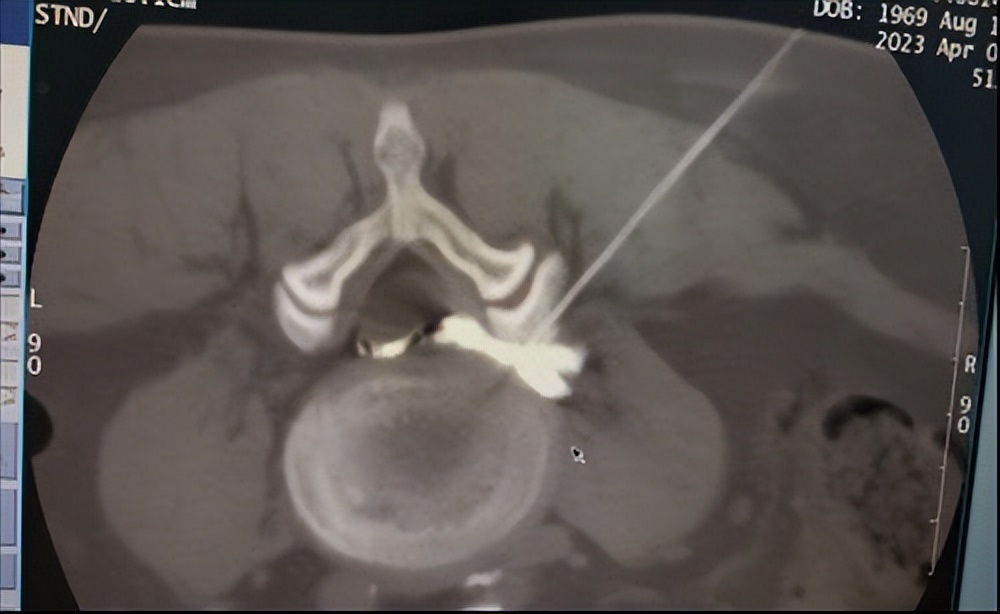

在与王阿姨及家属充分沟通、详细讲解病情、手术方式及预后情况后,针灸康复疼痛科主任张静为王阿姨确定了手术方案——CT引导下腰4/5椎间盘纤维环微创消融术+神经阻滞阵痛术+胶原酶溶解术。

张静介绍:“患者的腰椎间盘已经出现神经压迫,保守治疗效果不明显。我们的手术方式其实就是在CT的引导下用一根针将胶原酶注入病变的椎间盘,通过水解胶原酶被血浆中和吸收,从而使椎间盘突出物减小或消失,使得神经组织的压迫得以缓解或消除,临床症状就会得以改善或消失。”该微创手术具有创伤小(仅仅2mm左右穿刺口)、恢复快、不破坏脊柱稳定性、住院时间短等优势。

(CT引导下精准穿刺)